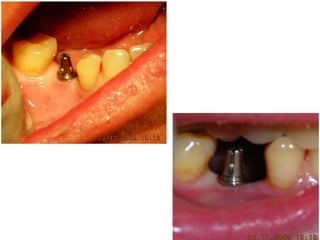

Dogmar Dasgupta,March,2009

Immediately after operation

On 11th.March,2009.

2

9

April,2012